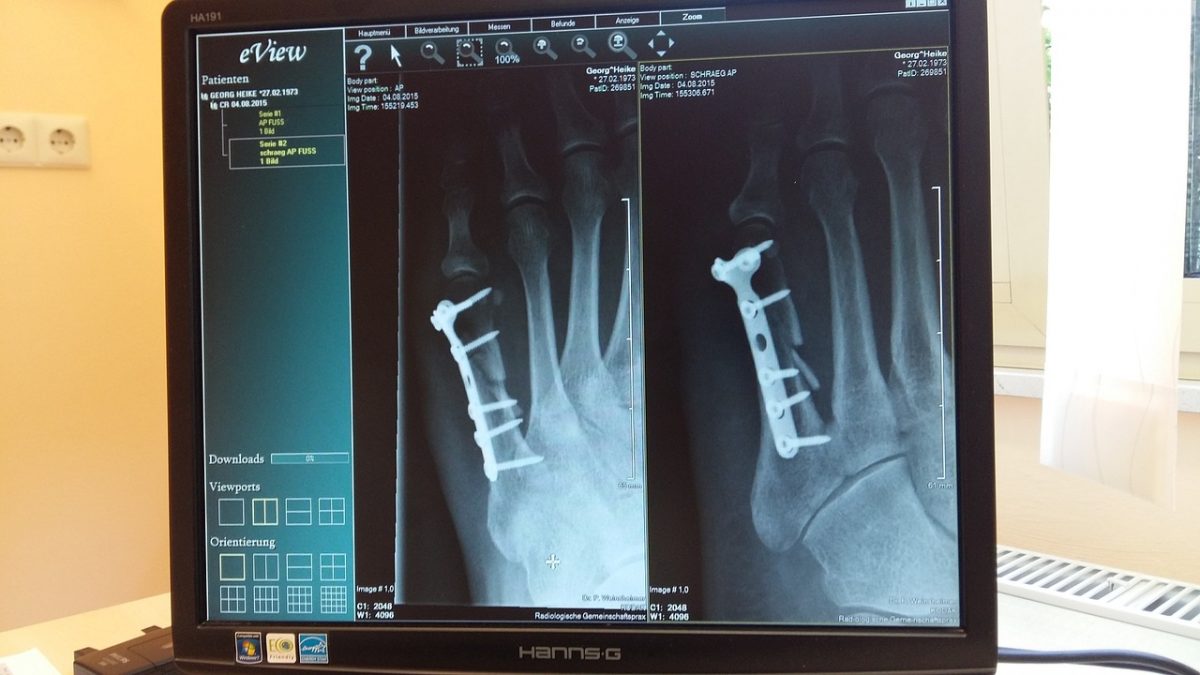

Zack Whittaker, a TechCrunch szerkesztője alapos írásban tárja fel azt a tragikus képet, amire egy német IT-biztonsággal foglalkozó cég, a Greenbone Networks jutott: többszáz kórház, egészségügyi szolgáltatóhely és képalkotó labor tárolja hanyag módon az általa létrehozott, illetve rábízott adatokat. A cikk szerint egymilliárd kép érhető el jelszó nélkül, ingyenesen letölthető szoftverekkel, és ez a szám naponta milliónyi felvétellel növekszik. Ami még ijesztőbb, hogy ezek a fájlok nem csak az adott CT vagy MR felvételt tartalmazzák,

hanem érzékeny adatok egész sorát teszik elérhetővé.

DICOM formátumú fájlokban ugyanis gyakran megtalálni olyan információkat, amelyek segítik a beteg beazonosítását. Ezekkel biztosítási vagy egyéb csalást lehet elkövetni, amerikai pácienseknél ehhez elég lehet a név és a társadalombiztosítási azonosító ismerete. Ezek mellett a beteg kórtörténete is szerepelhet, ami sokak számára talán még kellemetlenebb, mint annak a kockázata, hogy az adataikkal bűncselekményeket követhetnek el.

Egy Nyugat-Európát megjárt, Magyarországon az állami és a magánegészségügyben is dolgozó sebész a Rakétának elmondta: "a DICOM itthon is elterjedt formátum. Egy-egy ilyen mappa jellemzően 5-600 képszeletet tartalmaz, mindegyikhez hozzárendelve a páciens neve, születési dátuma, esetleg TAJ-száma, illetve a felvételt készítő gép típusa és annak beállításai.” Ennek az előnye természetesen az, hogy bárki bármikor dolgozik a fájllal, gyorsan el tudja kezdeni használni azt.